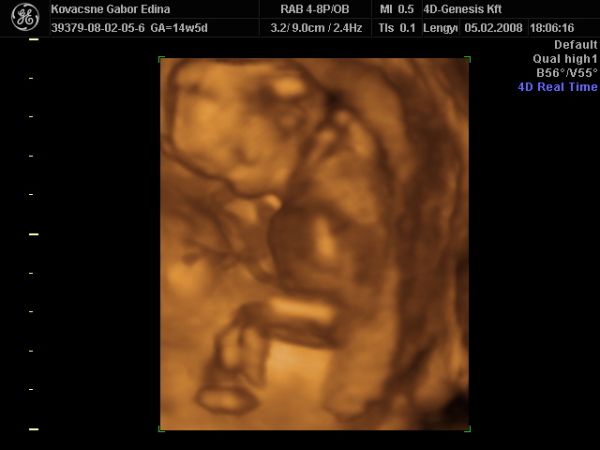

KISFIÚ 100%!!!

Annyira jó volt lányok a mozizás. Édesen kicsi a hely, de szépen berendezett, kellemes környezet. A hölgy, aki csinálta az UH-t nagyon kedves (néha mondjuk már sok), de inkább ilyen legyen

Mondta, hogy imádja az ilyen pici terhességeket, amikor még egyben lehet az apróságokat látni.

Babussal minden rendben. Ficánkolt össze-vissza. Lába keresztben, karja a feje mögött, mint aki fekszik egy nyugágyban a tengerparton. Hatalmas pocija van...kis beles

Ismét egy héttel nagyobb volt, 15+5 naposnak mérték. Ilyenkor már CRL-t nem néznek. Viszont 125 g, a könyv szerint egy 15 hetes magzat kb. 50 g...nem tudom mitől lehet.

Végig ébren volt, szopta a végén az ujját is. Imádom!

Ja, a kis kukiját pedig többször is megmutatta az én drágám, nem titkolózott hála istennek.